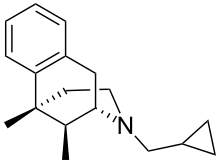

Morphinans

Morphinan series

- 3-Hydroxymorphinan

- 4-Chlorophenylpyridomorphinan

- Cyclorphan

- Levargorphan

- Levorphanol

- Levophenacylmorphan

- Levomethorphan

- Methorphan (racemethorphan)

- Morphanol (racemorphanol)

- Norlevorphanol

- N-Methylmorphinan

- Oxilorphan

- Phenomorphan

- Proxorphan

- Ro4-1539

- Stephodeline Xorphanol

Structures

| Other morphinans | ||||

|---|---|---|---|---|

4-chlorophenylpyridomorphinan 4-chlorophenylpyridomorphinan |

Cyclorphan Cyclorphan |

Dextrallorphan Dextrallorphan |

Levargorphan Levargorphan |

Levophenacylmorphan Levophenacylmorphan |

Levomethorphan Levomethorphan |

Norlevorphanol Norlevorphanol |

N-Methylmorphinan N-Methylmorphinan |

Oxilorphan Oxilorphan |

Phenomorphan Phenomorphan |

Dextromethorphan Dextromethorphan  levomethorphan levomethorphan |

Morphanol Morphanol |

Ro4-1539 Ro4-1539 |

Stephodeline Stephodeline |

Xorphanol Xorphanol |